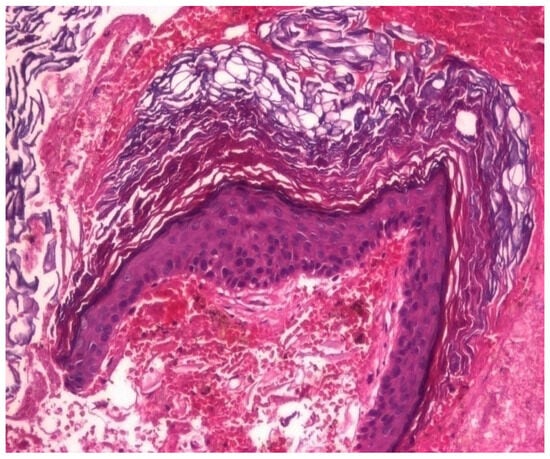

3.1.3. Analysis of Histopathologic and Immunohistochemical Results

| Histopathologic Aspects | Number of Patients |

|---|---|

| Cholesteatom | 276 |

| Polip | 180 |

| Tympanic membrane mucosa chamber, epithelium with apocrine-like cells, and chronic inflammatory infiltrate | 128 |

| Cell Types | Percentage |

| Lymphocytes T | 42.55% |

| Lymphocytes B | 31.45% |

| Macrophages | 26.00% |